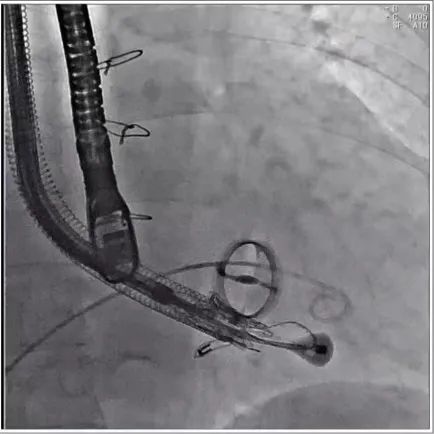

根据术前评估结果,郭应强教授团队为患者量身定制了手术策略,决定使用LuX-Valve Plus经血管三尖瓣置换系统开展手术治疗。手术在全麻下进行,采用经右侧颈静脉入路,在经食道超声和DSA的指引下调整输送器角度以达到正确位置,勾住前瓣后逐步释放盘片,盘片打开后顺利扎针,最终完成瓣膜植入,输送器撤出。术后超声提示人工三尖瓣同轴性良好,瓣架固定牢靠,无反流和瓣周漏,术后三尖瓣平均跨瓣压差为1 mmHg。

术后DSA造影